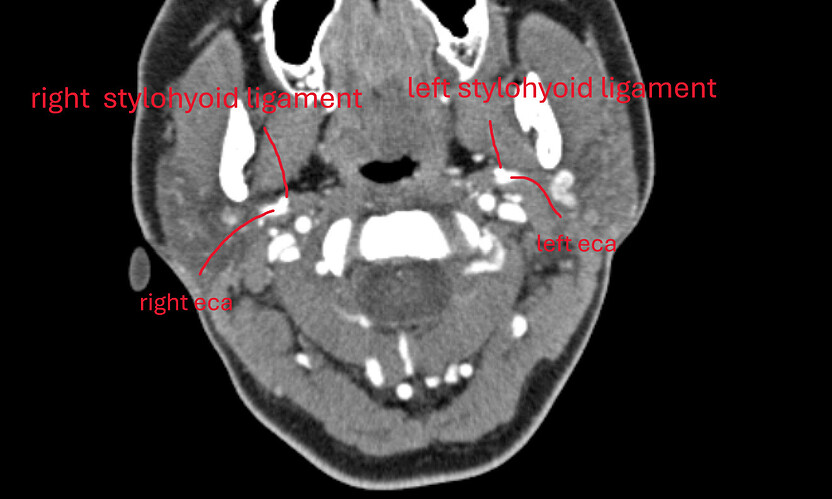

@eggisnotaplant see attached annotated imaging.

Stylohyoid ligaments are well-clear of your IJVs (i.e., they are not causing any direct compression of your IJVs). IJVs are pretty pancaked against C1 though on both sides. If you have intracranial hypertension symptoms I think a C1 shave could help. You do have collaterals formed on the back of your neck, which is often suggestive of IJV compression. Some radiology studies show that many people have collaterals and no intracranial hypertension symptoms, but if you do have these symptoms I’m not sure what else would be causing them besides the C1-IJV compression. Vagus nerves may be compressed between your IJVs and C1, which could cause dysautonomia symptoms. But so too could other things (e.g., CCI being one). I forgot to label it, but your right posterior digastric seems to add to some of the IJV compression on your right side - at the level of C1 and just below it.

BOTH calcified stylohyoid ligaments are in direct contact with your ECAs.

I think the mass you see may be a lymph node. I say this because there is the same mass on the other side that comes in and out of view just a couple slices further down. If it is a lymph node, I’m not sure if it’s within normal limits or not in terms of it’s size. It also may not be a lymph node, just my best guess.

@Jules I wouldn’t say they are fused (i.e., the stylohyoid ligaments ans ECAs) - I think the stylohyoid ligaments are just pressed against or resting against the ECAs. I’m seeing this a lot lately!